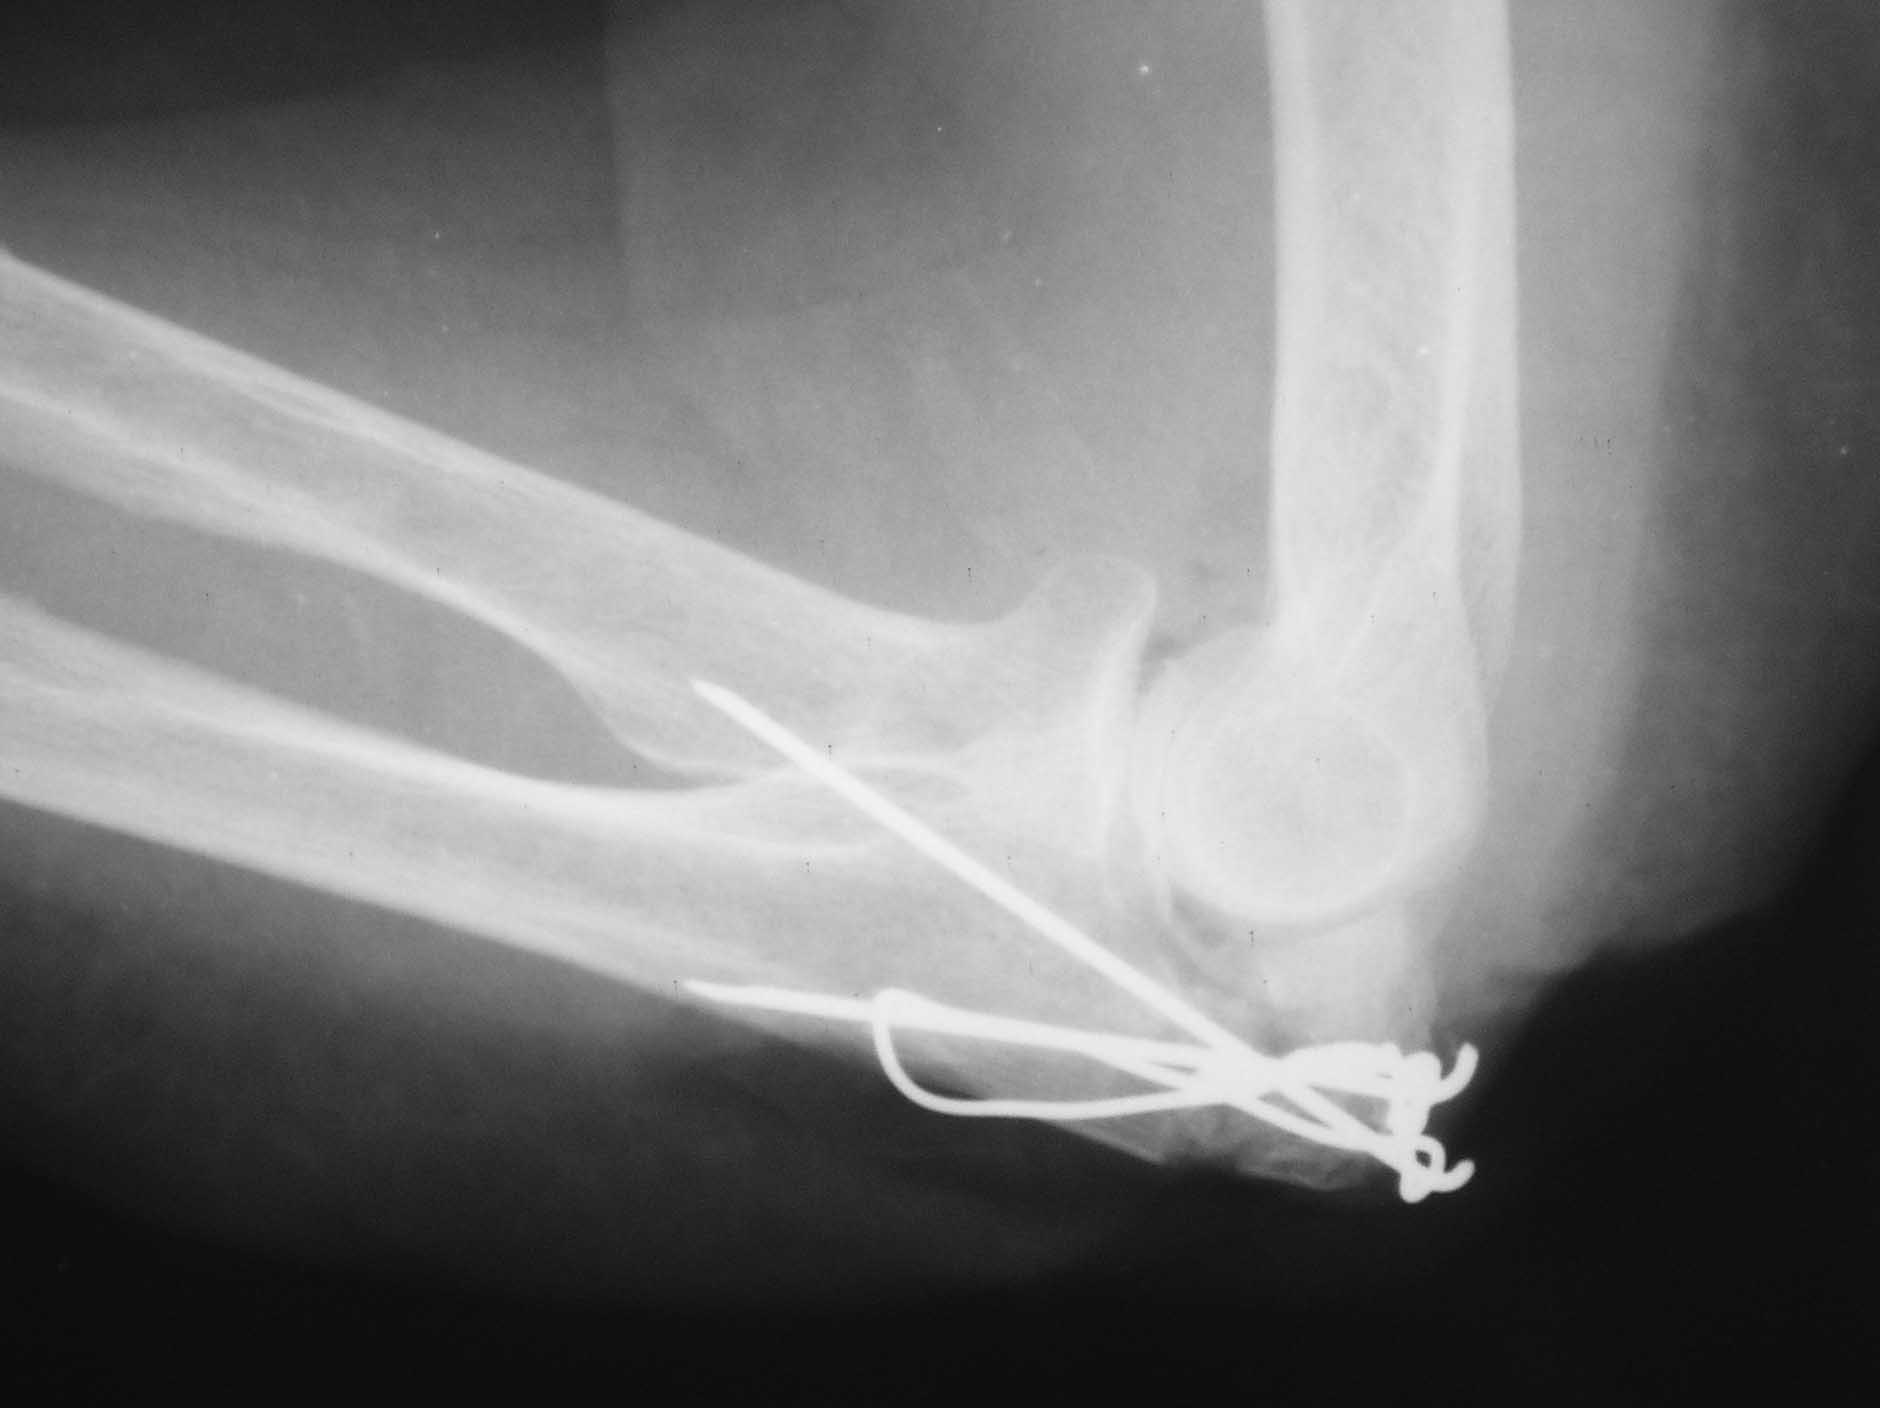

В послеоперационном периоде под личным контролем проводилась разработка движений в суставах правой верхней конечности. Рана зажила первичным натяжением. Больная выписана из клиники на 12 сутки после операции. Непосредственно в день выписки по настоянию «одного доктора» выполнена рентгенография локтевого отростка, на которой обнаружено расхождение костных отломков (на 2-3 мм (см. фото 5). Назначена врачебная внутрибольничная конференции по данному случаю, которая и проведена в ноябре 2013 года. На конференции приведены убедительные доводы об особенности клинического случая, обоснована необходимость остеосинтеза перекрестно проведенными спицами и проволокой, озвучены заключения двух известных на всю Россию профессоров-травматологов, которые подтвердили, что на рентгенограммах, сделанных в операционной «положение костных отломков локтевой кости удовлетворительное. Костные отломки в состоянии контакта друг с другом. Ось локтевой кости правильная. Учитывая преклонный возраст пациентки, следует признать возможным и допустимым выполненный вариант остеосинтеза локтевого отростка проволочной петлей и двумя спицами». Мнение «одного доктора» о необходимости повторной операции на конференции не поддержано ни одним из врачей. В решении конференции указано, что следует продолжить консервативное лечение пациентки под контролем врачей.

В последующие недели под личным контролем проводилась разработка движений в локтевом суставе. В конце декабря при контрольном осмотре в присутствии еще одного профессора и самого «одного доктора» выявлено: движения в локтевом суставе – 80/150°, пациентка довольна проводимым лечением, выполняет этой рукой все основные действия (умывание, причесывание, прием пищи и пр.), болей в локтевом суставе нет. На рентгенограммах – смещение костных отломков не увеличилось, положение металлофиксаторов – стабильное (см. фото 6). Промежуточный функциональный результат вполне удовлетворительный (фото 7,8). В настоящее время разработка движений в локтевом суставе продолжается.

4) Вероятно, следует напомнить, что продольная (по оси локтевой кости) компрессия в случае раздробления костных отломков недопустима. Именно в связи с этим проведение двух спиц параллельно друг другу со стягивающей петлей является противопоказанием при многооскольчатых (и тем более раздробленных переломах). Проведение двух спиц не параллельно, а перекрестно друг к другу как раз и не дает компрессии в момент натяжения петли. В свою очередь, проволока в этом случае выполняет роль стабилизатора положения одновременно и спиц, и промежуточных костных отломков, предотвращая смещение их в стороны. Подтверждением этому являются этапные рентгенограммы (выполненные в конце декабря), на которых отмечено стабильное положение костных отломков и металлофиксаторов, несмотря на разработку движений в суставе.